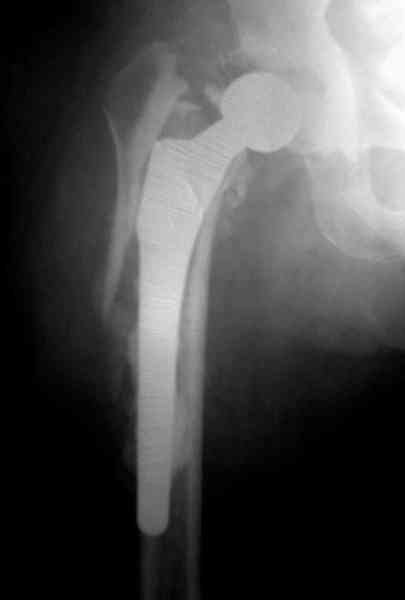

Приглашенный хирург установил ревизионный вариант бедренного компонента без замены ацетабулярного компонента, что осложнилось нагноением и свищами на уровне сустава и средней трети бедра. После двухгодичного безуспешного лечения перевязками и антибиотиками больная обратилась к нам на консультацию.

Повторная операция по удалению тотального протеза с irrigation&debridment, канал после очистки цемента обильно промыт и рассверлен римером.

Для спейсера в бедро использовал старый длинный бедренний компонент меньшего диаметра, облепленный со всех сторон цементом с антибиотиком.

№3-6 снимки с осложнением

и последние снимки.